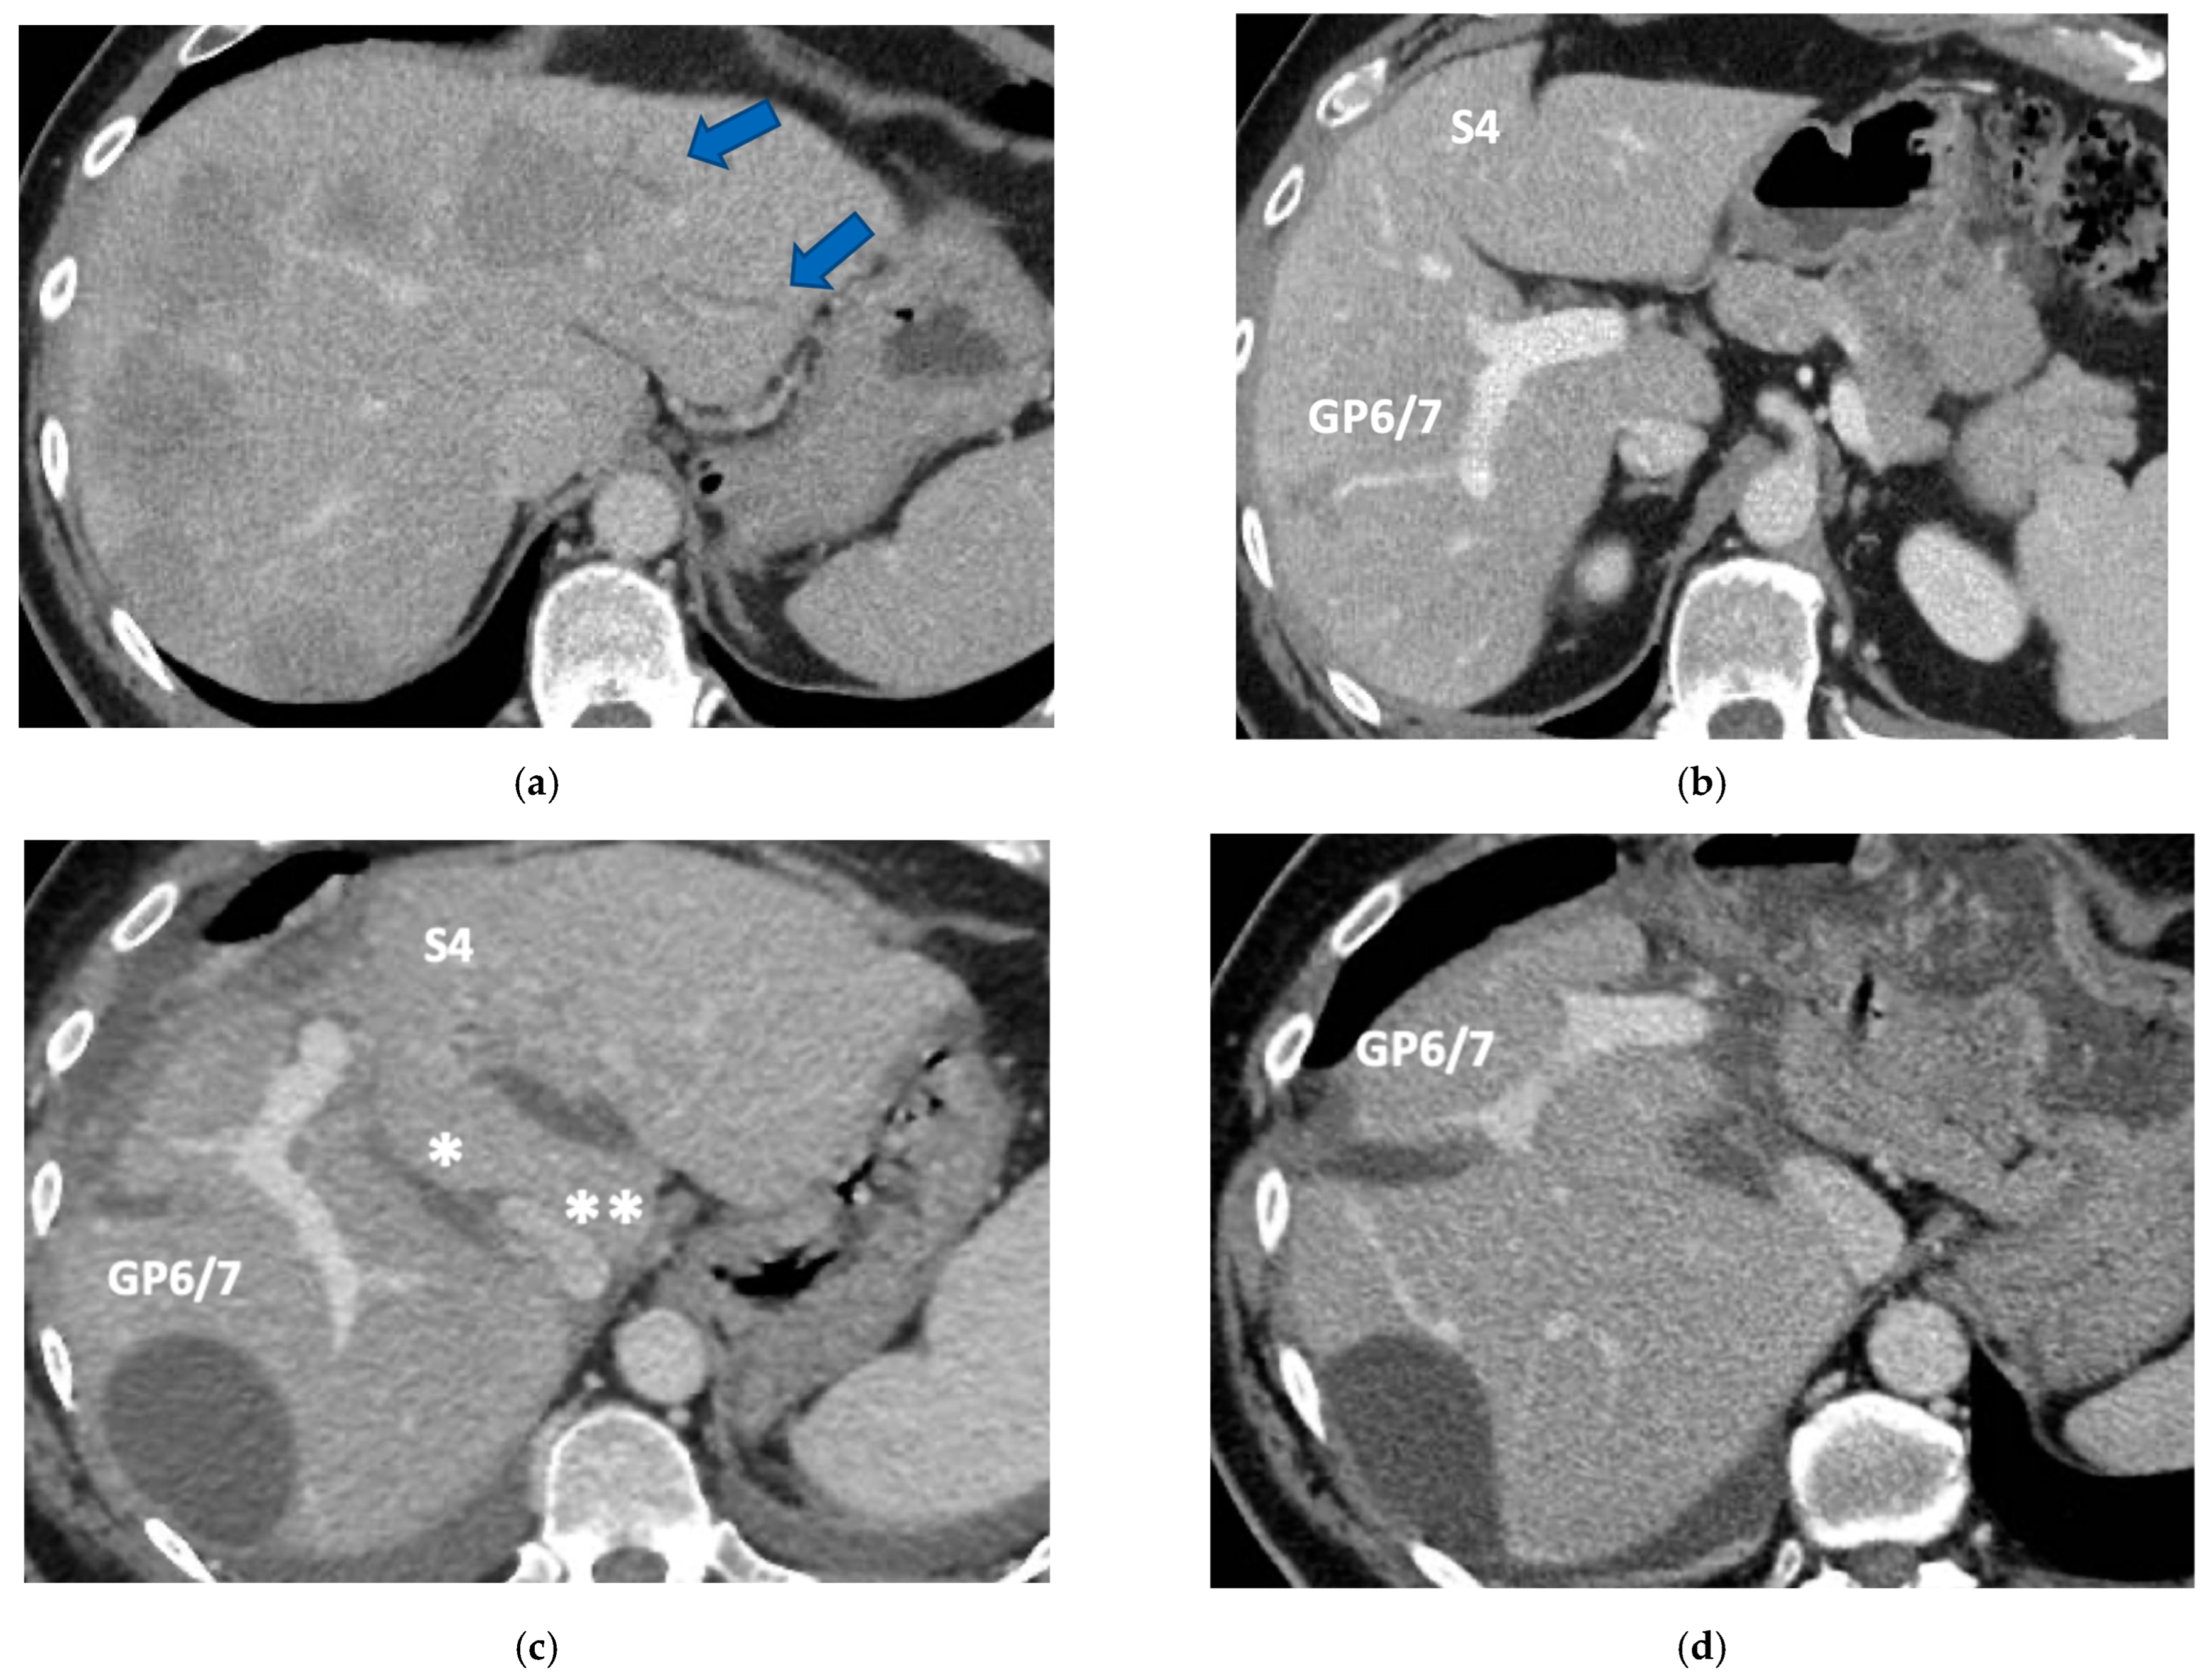

Figure 6. CT Images of PS-TSH with SS-PVE performed to treat 35 bilateral CRLMs. (a) Partial response after FOLFOXIRI + Bevacizumab 12 cycles; FLR (=S2/S3) volume is 15%. (b) Blue arrow points GP 5 after the first stage consisting of resection of S1/S4 extended to S2/S8/S5 plus metastasectomy of S2 with tangential resection of LHV. (c) Fourteen days after stage 1 SS-PVE was performed on the right liver preserving GP 5 (blue arrow); 37 days after SS-PVE FLR (=S2/S3/S5) increased up to 37%. (d) Blue arrow points GP 5. Twenty-five months after PS-TSH with SS-PVE the patient is disease free; the liver’s only disease recurrence was successfully treated with another 3 liver resections (2 on the right liver and 1 on the left). Abbreviations: PS-TSH: parenchyma-sparing TWO-STAGE hepatectomy; SS-PVE: super-selective portal vein embolization; CRLM: colorectal liver metastases; FLR: future liver remnant; S: segment; GP5: glissonean pedicle for segment 5; LHV: left hepatic vein.

3.3. PS-TSH with SS-PVE

Super-selective portal vein embolization was performed in three patients since the resection of first-order GPs was deemed not necessary and a TWO-STAGE major PSH with SS-PVE was planned. Percutaneous PVE was achieved under US guidance via an ipsilateral approach through the tumor-bearing liver in two patients and via a contralateral approach through the future remnant liver in one patient. The accesses were respectively by S6, S5 and S3 portal vein branches under US guidance and local anesthesia. In all three cases S1/S4 were anatomically resected en-bloc with MHV at the first stage (MLP). Super-selective PVE consisted in embolization of portal branch for S6/S7/S8 in one case, for S7/S8 in one case and for S5/S8 in one case. The second stage was performed 58, 57 and 63 days after the first stage and consisted in the resection of S6/S7/S8 with RHV skeletonization in one case (see Figure 6 and Figure 7), in resection of S7/S8 partially extended to S5/S6 en-bloc with RHV reconstructed with an end-to-end anastomosis in one case (see Figure 8) and in resection of S7/S8/S5 en-bloc with RHV reconstructed with end-to-end anastomosis in another case. No complications occurred after surgery and patients were discharged from the hospital on the 11th, 11th and 17th post-operative day. The primary was resected at the time of the first stage (right hemicolectomy) in two cases and before the first stage (left hemicolectomy, “primary first” strategy) in one case.